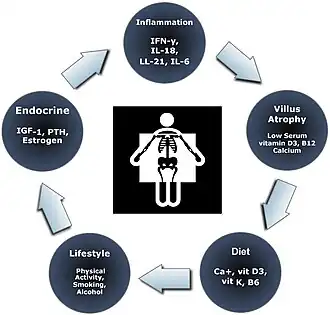

Nutritional status in coeliac disease may be compromised due to lower intake, maldigestion and malabsorption, leading to nutritional deficiencies. Common deficiencies in coeliac disease include iron, folate, zinc, vitamin D, and vitamin B12.[14][18] Vitamin D deficiency can cause secondary hyperparathyroidism. Hyperoxaluria and kidney stones can be caused by malabsorption of fats and peptides.[18] Iron deficiency may lead to anaemia, which is one of the most common extraintestinal presentations of coeliac disease.[17] Coeliac disease also often affects the bones, causing low bone mass density (osteopenia) and osteoporosis. Causes of bone changes in coeliac disease are believed to be caused by malabsorption, inflammation and autoimmunity.[16]

If left untreated, coeliac disease can affect hormones, causing delayed periods or puberty and reproductive disorders.[14][16] Coeliac disease is associated with infertility and complications during pregnancy such as intra-uterine growth restriction and spontaneous abortion. Reproductive disorders are thought to be caused by nutritional deficiencies, particularly zinc, iron, folate and selenium deficiencies in coeliac disease.[18]